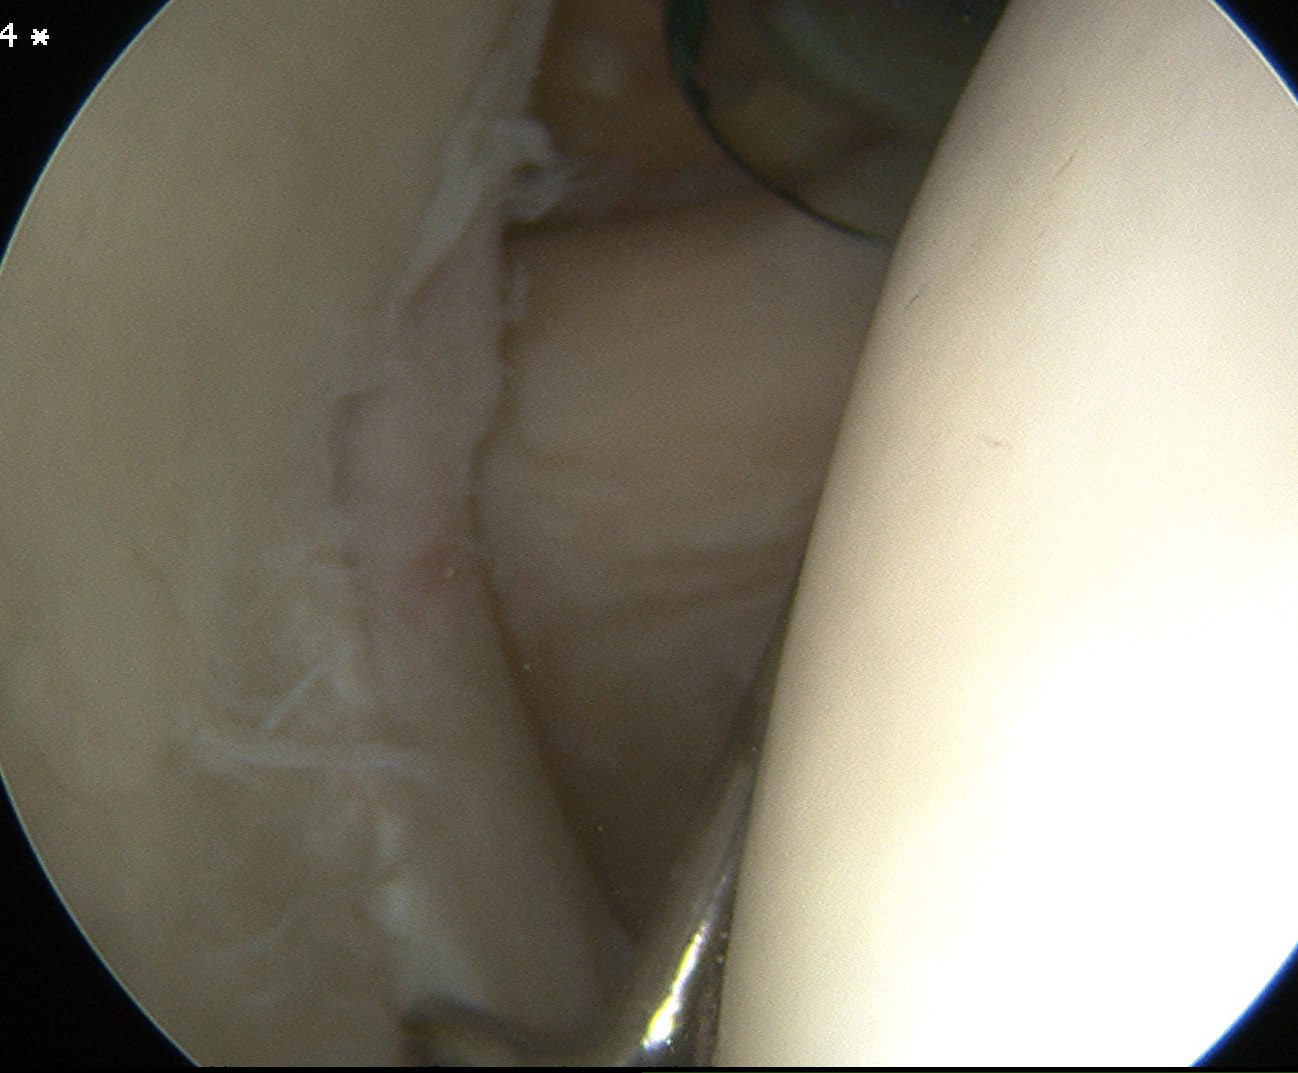

Labrum

Anterior inferior labral tears |

Below equator 3 - 6 o'clock |

Mobilize anterior labrum

Mobilize labrum

Labral mobiliser / rasp

- labral tear can be obvious, but may have partially healed or healed medially

- change camera to anterosuperior portal for better view

- mobilize until can see subscapularis muscle underneath

- need to be able to advance labrum medially and superiorly for repair